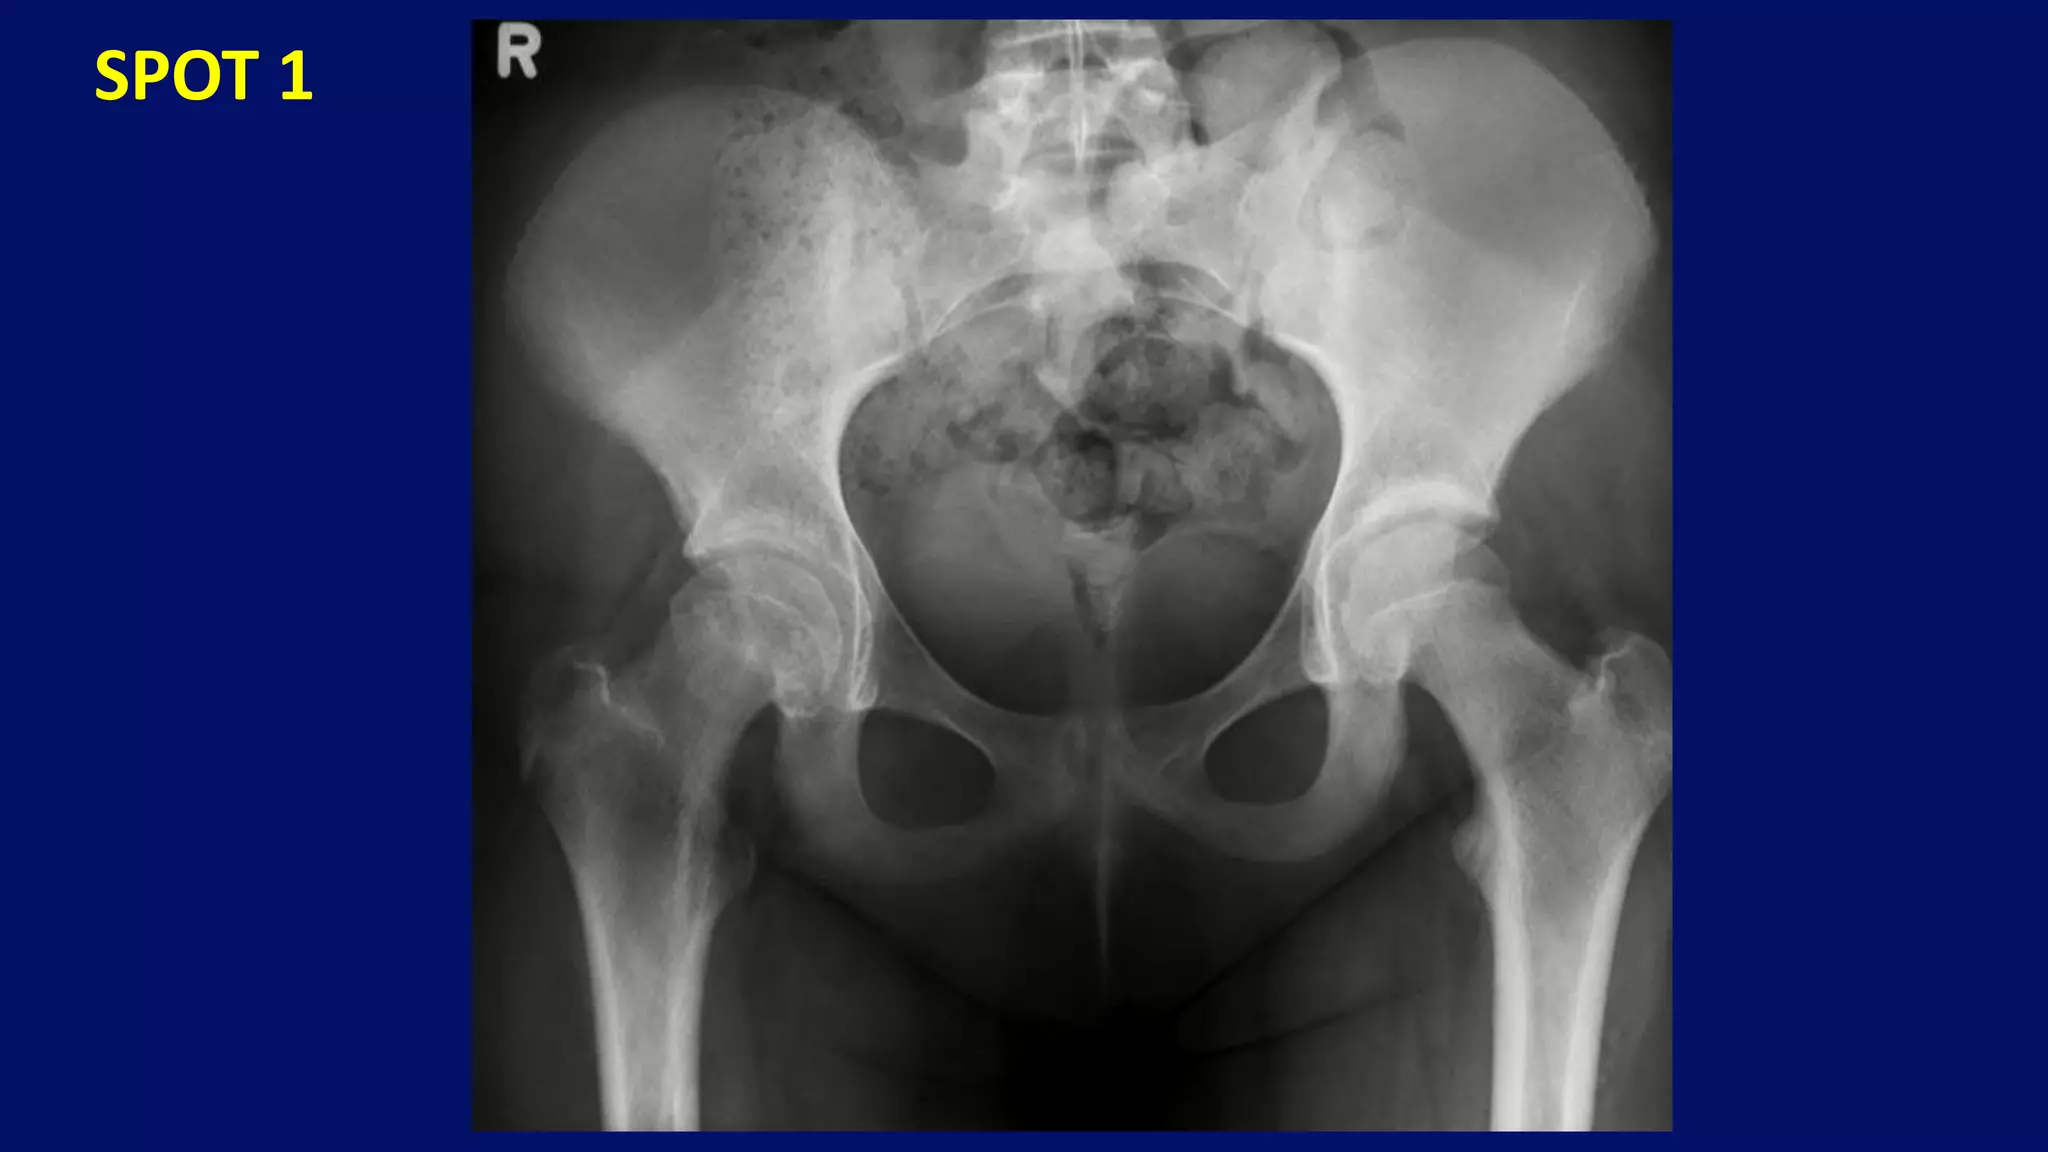

SPOTS

SPOT 1